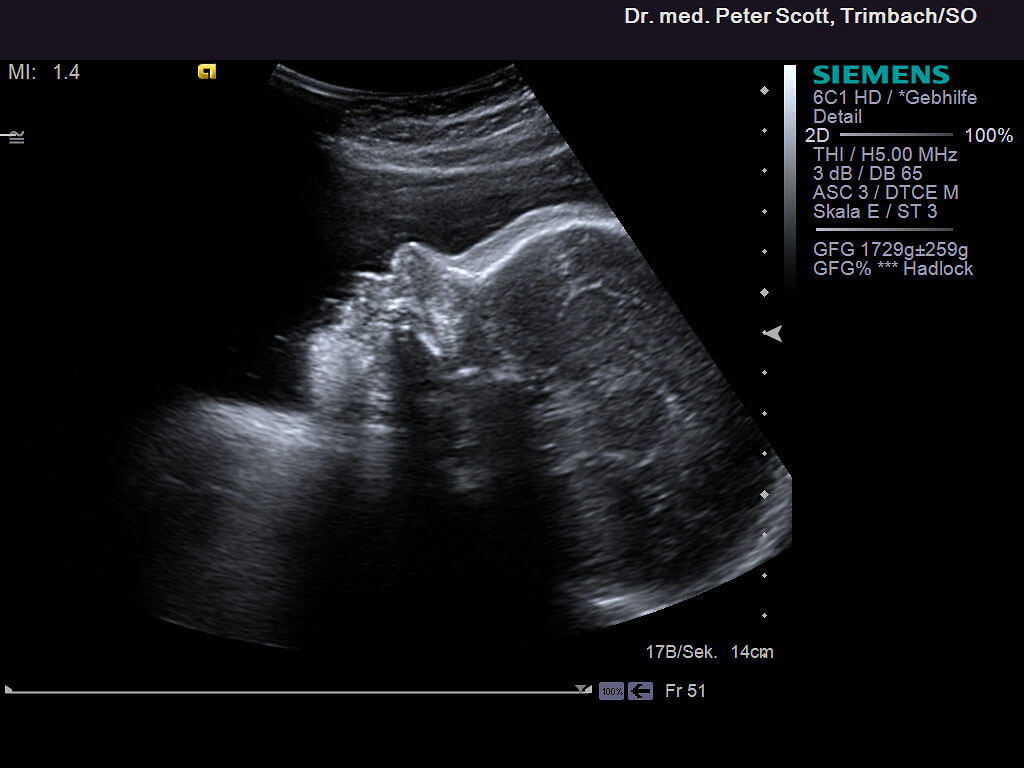

Ultraschall in der Schwangerschaft

• ab der 12. SSW durch die Bauchdecken

• Bestätigen des normalen Schwangeschaftsverlaufs

• Risikoberechnung für Chromosmenstörungen (Down Syndrom/Mongolismus)

• Erkennen von Missbildungen, Plazentalokalisation, Lagekontrolle

• Beurteilen des fetalen Befindens (Fruchtwassermessung, Kindsbewegungen)